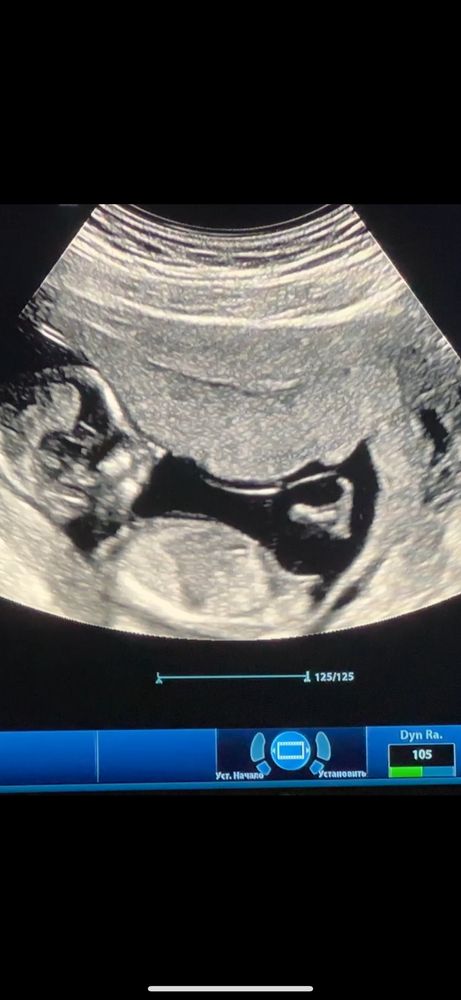

Мальчик или девочка?🤔

Как то не очень понятно🤔если лучше разглядеть то девчонка выходит у вас)

как-то тут 50 на 50 по наклону. с первого взгляда кажется мальчик, Но если линию провести то больше и на девочку похожа

Похож на мальчика, половой бугорочек под углом к спине.

первое, что увидела на фото-писун))

Azrmif, только это не он, а половой бугорок) у девочек он точно такой же.